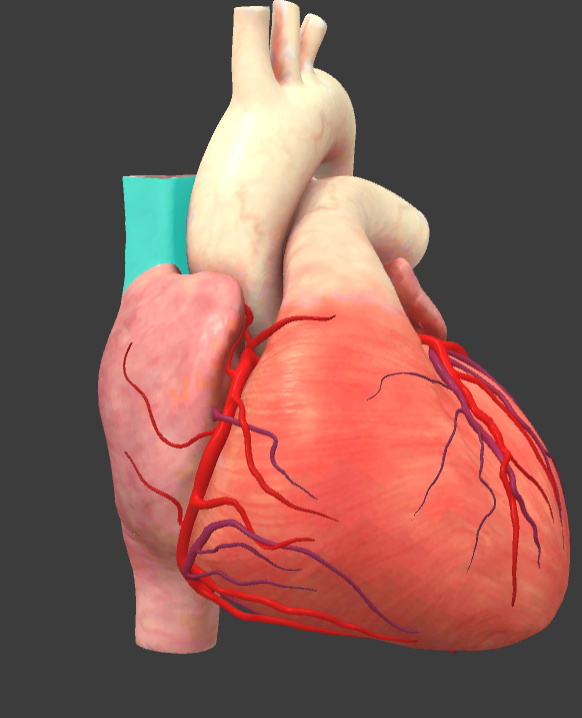

What is the name of the main vessels that supply the heart tissue with blood?

Coronary arteries

Arch of aorta

Brachiocephalic trunk

Inferior vena cava

Left auricle

Pulmonary trunk

Right auricle

Superior vena cava

Right coronary a.